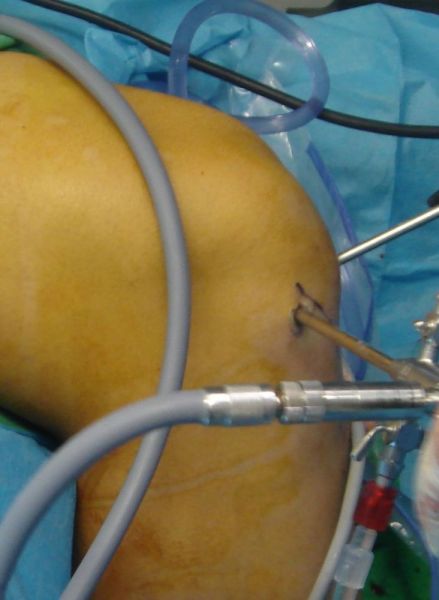

I. Before the surgery , lateral x-ray of the knee shows the chondroma (red arrow) II. Post-surgery, lateral x-ray of the knee shows that the chondroma has been removed III. Post-surgery, the photo (posterior site of the knee) is showing the specific approach that has been used for the operation.